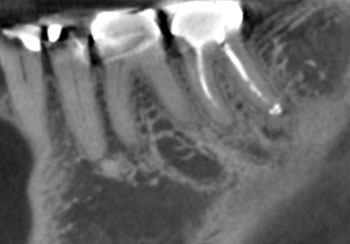

Fig. 7: Recall PA.

Case 3: A lateral lesion with a superficial crack

This patient presented for a second opinion after an endodontist recommended extraction for tooth #31 because of a VRF on its distal root. A deep isolated probing defect, a cervical sinus tract, the lateral position of the periradicular lesion and the prior placement of a full crown because of cracks in the tooth’s distal enamel marginal ridge likely contributed to the prior diagnosis of VRF.

A new diagnosis of previously treated and chronic apical abscess was made, but the possibility of a VRF was discussed with the patient. RCT was initiated. Internal examination of the pulp chamber reassuringly revealed that a crack on the distal wall of the pulp chamber did not extend to the pulpal floor. Treatment was completed in three visits using a calcium hydroxide intracanal medicament. Treatment and postoperative radiographs revealed a sharp dilaceration of the distal root, likely focusing the bony lesion toward the distal surface, not toward the root apex. Four months later, soft tissue and bony healing were confirmed.

Fig. 9: Preop PA.